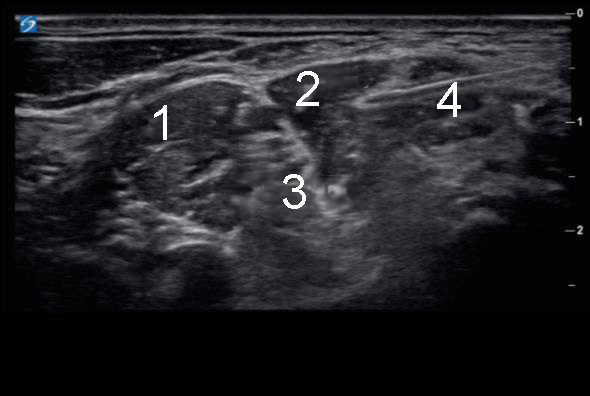

Left Interscalene Block with Needle 1 Image

1. Anterior Scalene

2. Middle Scalene

3. Interscalene Brachial Plexus

4. Needle